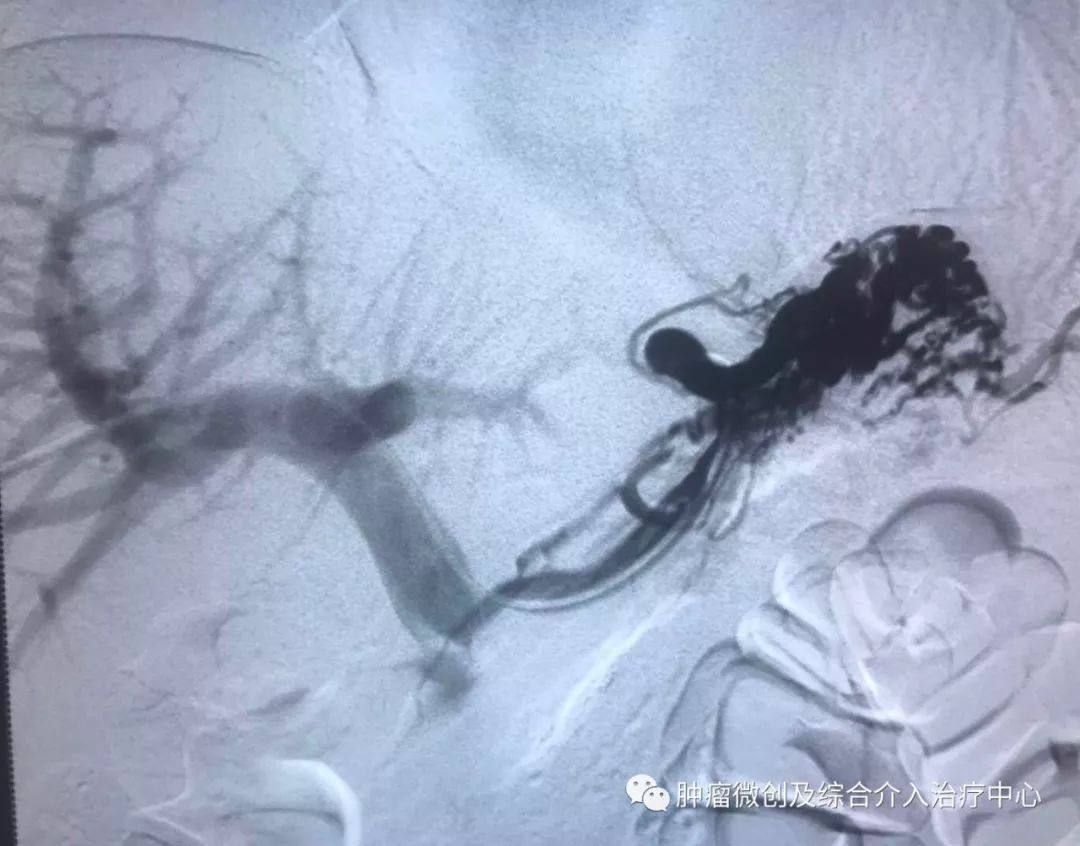

(介入栓塞病变血管后,DSA示肿瘤病变血管栓塞好,血管走向清晰,出血停止)项目介绍:头颈部良、恶性肿瘤临床常见,其良性见于鼻咽纤维血管瘤,恶性者见于鼻咽、鼻窦癌,颈部转移性肿瘤等; 传统止血治疗疗效有限,给患者及家属带来极大的精神压力,介入手术栓塞病变血管可达到确切的止血效果,并致病变缺血萎缩。04急性肺栓塞介入手术治疗